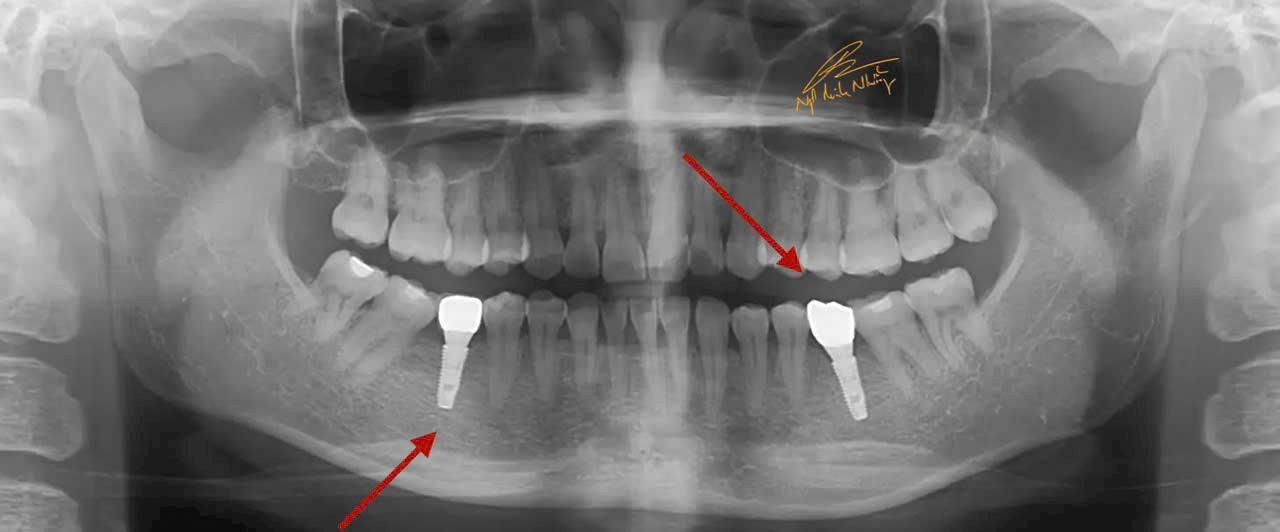

Teo xương hàm : Khi mất răng, xương hàm không còn được kích thích bởi các lực nhai, dẫn đến việc mất dần chất lượng và khối lượng xương tại khu vực mất răng. Điều này có thể làm thay đổi khuôn mặt và làm giảm khả năng lắp răng giả hoặc cấy ghép sau này.

Di chuyển các răng còn lại : Khi mất răng, các răng còn lại có thể bị xô lệch, làm thay đổi cấu trúc của hàm và gây ra các vấn đề về khớp cắn.

Cấy ghép răng (Implant) : Đây là phương pháp phổ biến và hiệu quả nhất để phục hồi răng đã mất. Cấy ghép răng giúp phục hồi chức năng nhai và ngăn ngừa tình trạng teo xương hàm. Cấy ghép được cấy vào xương hàm và có thể lắp răng giả lên đó.